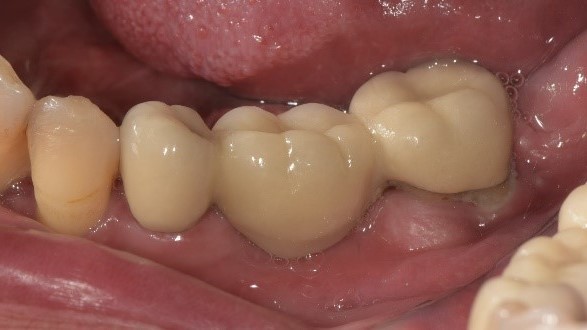

治療後